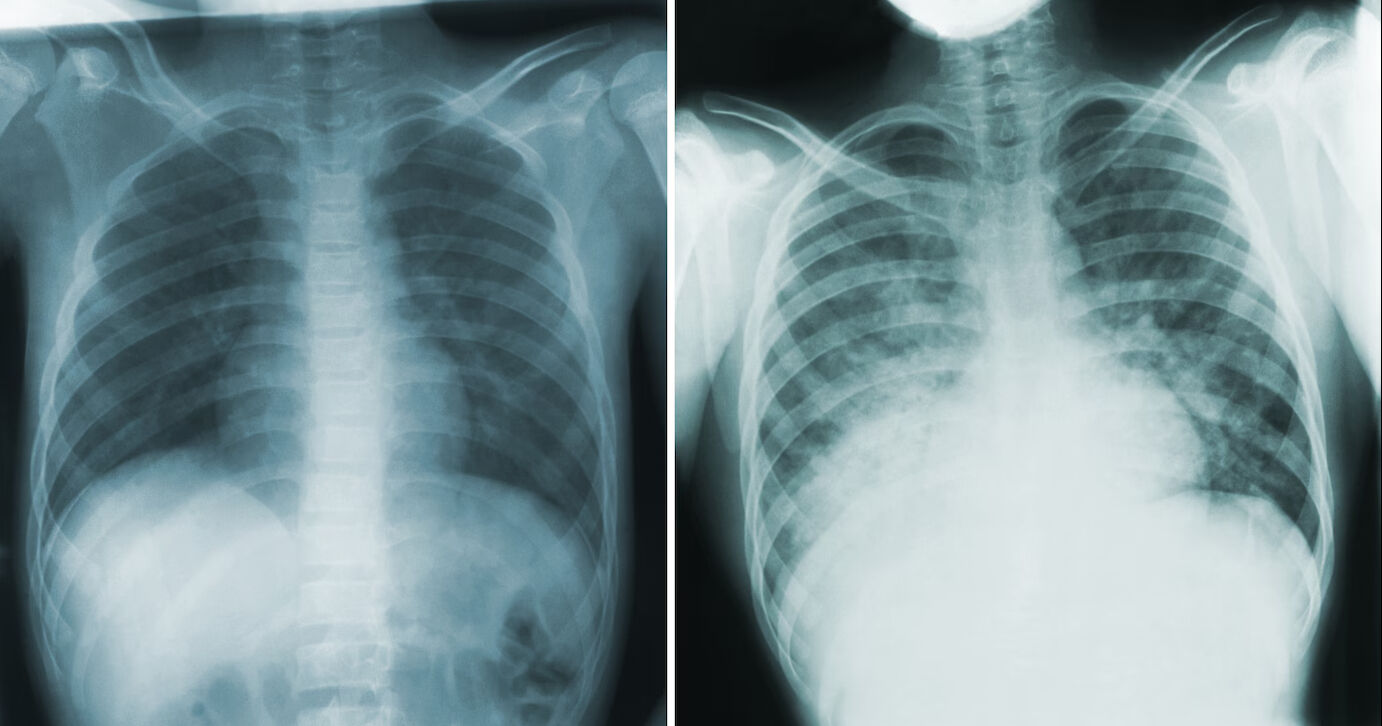

Akciğer vebası, vebanın en öldürücü ve en az görülen türü olarak tanımlanıyor. Hastalık, dağ faresi gibi memelilerde bulunan ve hayvanlardan insanlara bulaşabilen "yersinia pestis" bakterisinin akciğere yerleşmesiyle zatürreye neden oluyor.

Solunum yoluyla yayılan damlacıklar aracılığıyla insandan insana bulaşabilen akciğer vebası, 1346-1353 yılları arasında milyonlarca can kaybına yol açmıştı. Salgının kesin kaynağına dair farklı teoriler ortaya atılmış ancak net bir sonuca ulaşılamamıştı.